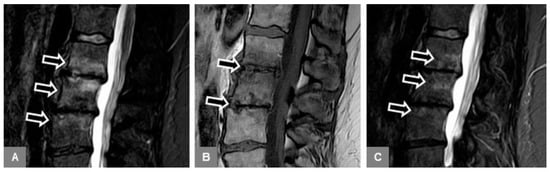

3.6. Modic Type 2 and 3 Endplate Changes

3.5. Appearance of the Intervertebral Disc